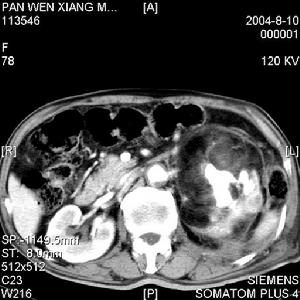

(2)CT檢查:因單靠腎血管造影不能確切地區分是XGPN、無血管性孤立腫塊或是壞死性無血管的腺癌。而CT掃描檢查可清楚顯示腎內多個結節狀或較大腫塊樣低密度病灶,並可見腎盂或集合管系統的結石和鈣化灶。局限型XGPN尚有以下徵象:

①腎一極增大變形,其中有囊狀密度區,CT值範圍-15~+30Hu,此取決於脂質的量,但不呈真正的脂肪密度。注藥後示明顯的病灶周邊增強係為多血管的肉芽組織圍繞所致。含脂質的黃色瘤病灶內不增強。

②局限性腎腫塊,突出腎輪廓之外,等密度或略高密度,酷似腎癌,但增強後強化不明顯由於周圍腎實質明顯強化,病灶境界變得很清楚,相對的呈現低密度,此不同於腎癌。

③局限性的病變形態多為類圓形,此反映病變緩慢生長的特點。

④易侵犯腎周間隙和腰大肌CT顯示腎筋膜增厚,病灶與腰大肌粘連。